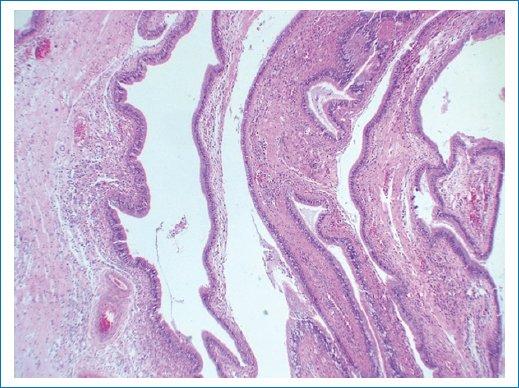

El diagnóstico histopatológico reportó un granuloma de colesterol, negativo para malignidad. Descripción microscópica: al corte histológico se identifica una lesión quística cuya pared está compuesta por tejido conectivo e infiltrado inflamatorio mixto. Se encuentra revestida por epitelio columnar ciliado pseudoestratificado con ocasionales células caliciformes. Se observan escasos focos revestidos por epitelio plano estratificado no queratinizado. Se identifican espacios elongados en el tejido, los cuales son remanentes de cristales de colesterol después de su proceso histológico. Los espacios están asociados a una reacción a cuerpo extraño, tejido de granulación y abundantes hemosiderófagos. Integrando los hallazgos microscópicos con el antecedente de cirugía, se puede establecer el diagnóstico de quiste quirúrgico ciliado y granuloma de colesterol con una posible patología primaria de quiste dentígero (Figs. 2 a 4).

Figura 3. Corte histológico en el que se observan escasos focos revestidos por epitelio plano estratificado no queratinizado.